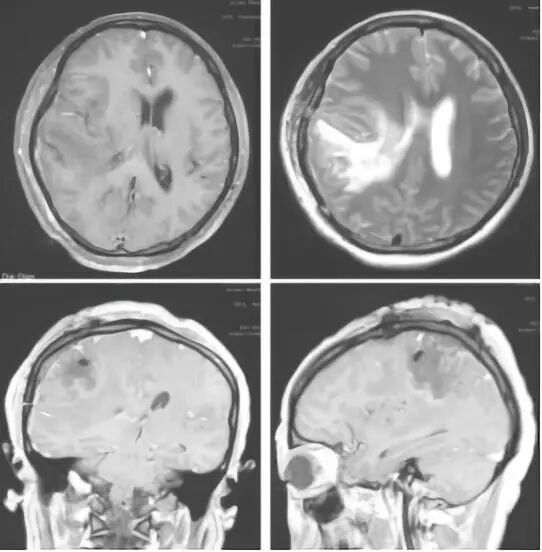

图1. 第一次术前MRI图像(2017.1.11)

图2. 第一次术后颅脑MRI图像(2017.1.22)